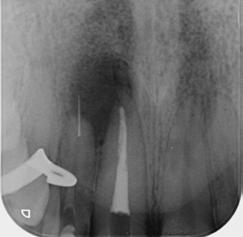

This is not a “Terminal Dentition”. It is interesting to see the increase in patients being advised that Periodontitis is not treatable or that treatment is somehow expensive and ongoing maintenance is difficult/unachievable. These patients are usually advised to receive implant treatment as an alternative.

This patient first presented in 2016 at the age of 33 years. He was a former smoker (quit two years prior to the initial presentation). He presented with generalised deep pocketing and advanced loss of attachment.

Radiographic assessment showed generalised moderate to advanced bone loss with most teeth showing bone loss to more than 50% of the root length. Given the established loss of attachment in relation to his relatively young age, this patient was diagnosed with generalised aggressive periodontitis. According to the 2017 Classification of Periodontal Disease, he would be Stage III, Grade C Periodontitis.

The patient was managed with non-surgical periodontal debridement. Two months later, he presented with an encouraging reduction in periodontal probing depth (PPD). There were 85% sites with PPD 1-3mm, 15% sites with PPD 4-5mm and no sites with residual PPD > 6mm. The patient showed excellent plaque control measures and his bleeding on probing score was 1%. The patient has been placed on a six-monthly periodontal maintenance program with the periodontist. He also sees his general dentist once annually. The OPG images dated 2016 and

2023 show stable bone levels with no evidence of further bone loss.

The patient had orthodontic treatment between 2018-2020 to address the flaring and spacing of his teeth, which was a cosmetic concern to him (orthodontic treatment done by Dr Frank Furfaro). Long-term evidence shows that we, as dental clinicians, are not accurate at determining the prognosis of periodontally compromised teeth (McGuire 1996). We may also be hasty at labelling such teeth as “hopeless”. The threshold at which we

decide to extract teeth due to periodontal disease may be too low (Splieth 2002). There is no evidence on the other hand that dental implants have longer survival or less complications or better cost compared to periodontally treated teeth.